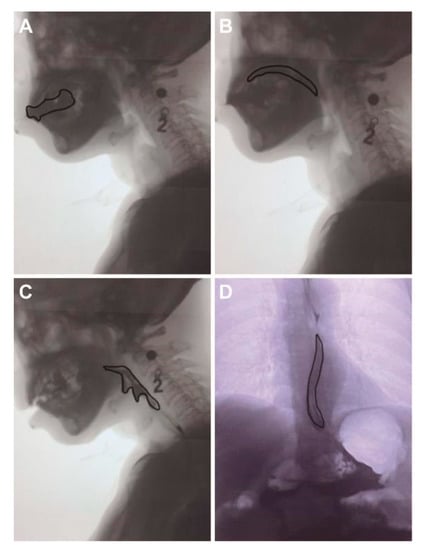

2.3.2. Swallowing Function

| Phases of Swallowing | Start Point | End Point |

|---|---|---|

| Oral preparatory phase | The food was processed in the oral cavity | |

| Oral propulsive phase | The tongue voluntary presses the collected bolus/saliva against the palate | Bolus passing the ramus of the mandible |

| Pharyngeal phase | Bolus passing the ramus of the mandible | The upper esophageal sphincter relaxation |

| Esophageal phase | The upper esophageal sphincter relaxation | The bolus into the stomach |